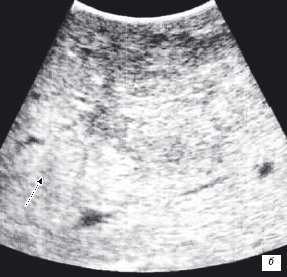

У 5 (41,7%) из 12 пациенток образования в печени имели гиперэхогенную, гомогенную структуру с четкими и ровными контурами размером от 5 до 12 мм в диаметре, которые были интерпретированы как доброкачественные образования печени — гемангиомы (табл. 2). У 4 (33,3%) пациенток образования имели анэхогенную гомогенную структуру, с четкими и ровными контурами, с гладкой внутренней выстилкой и эффектом усиления эхосигнала, размером от 3 до 11 мм в диаметре, и были интерпретированы как кисты. В 3 (25%) случаях в печени были выявлены гипоэхогенные образования солидной гетерогенной структуры с нечеткими, но ровными контурами размером от 10 мм в диаметре (рис. 1) до 22×17×15 мм в одном случае, расположенное на диафрагмальной поверхности печени, которое «самоампутировалось» в процессе исследования и при срочном гистологическом исследовании оказалось метастазом аденогенного рака (рис. 2).

Рис. 1. Эхограмма. Интраоперационное УЗИ печени (стрелкой указан метастаз рака яичника).